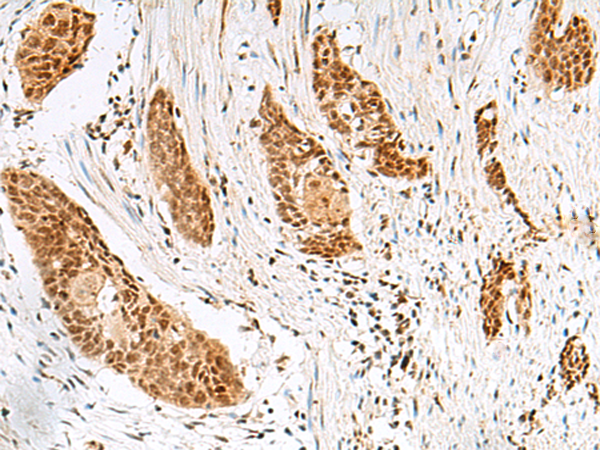

IHC positive control:

IHC Recommend dilution:

50-300